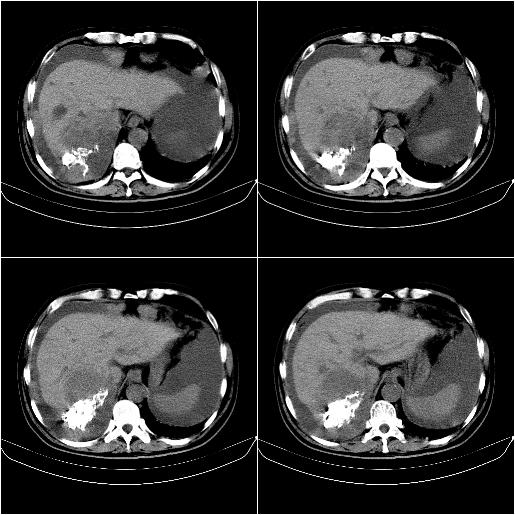

m,67y,肝癌9月,介入术后3月。现腹胀、纳差、腹泻。

1)肝癌介入治疗术后碘油沉积不良。2)门静脉瘤栓形成,腹膜广泛性转移。3)肝硬化,脾大,腹水。4)慢性胆囊炎。